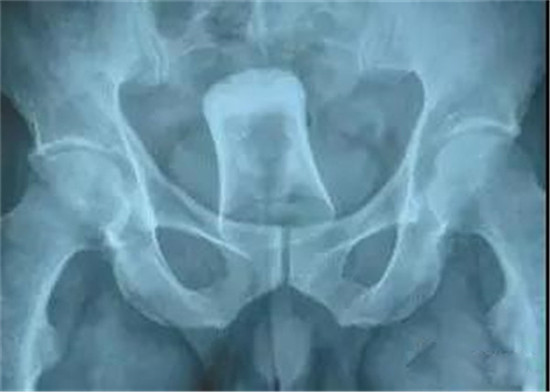

大肠里的擀面杖。男性

这是做饺子皮用的擀面杖。对,全部塞进去了。你知道怎么看男女吗?看骨盆的角度。

取出的方法如同上面。